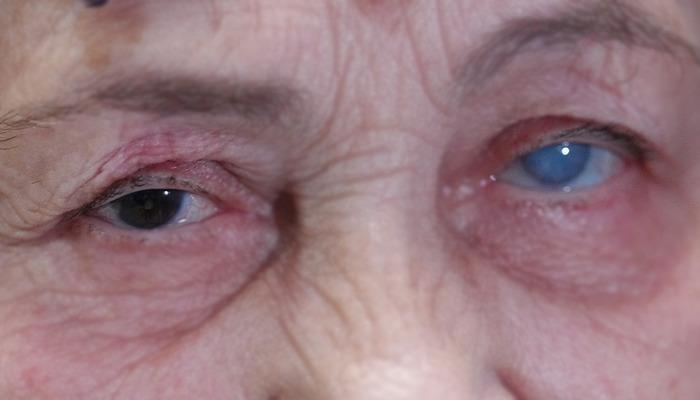

Sisler içinden aydınlığa kavuştu! Resmen ikinci kez hayata gözlerini açtı…